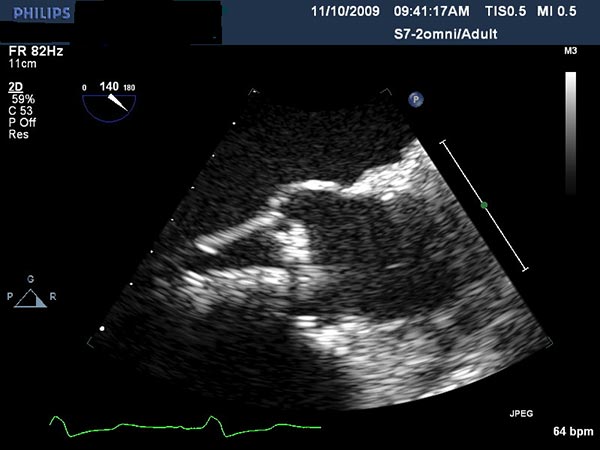

Echocardiography is important to confirm the severity of aortic stenosis, rule out bicuspid aortic valve (which a relative contra-indication) and to size the aortic annulus and left ventricular outflow tract (LVOT) (Figure 1). It is also necessary to assess for concomitant Mitral valve disease. Mild to moderate mitral regurgitation (MR) is frequently associated with AS in elderly patients but does not usually require any surgical intervention and does not represent a contraindication for TAVI. However, severe MR with bulky mitral annular calcification involving the LVOT has been associated with worse midterm outcome and increased risk of para-valvular leak (2).

Figure 3. Direct echocardiographic visualization of the left ventricular outflow tract during valve insertion.